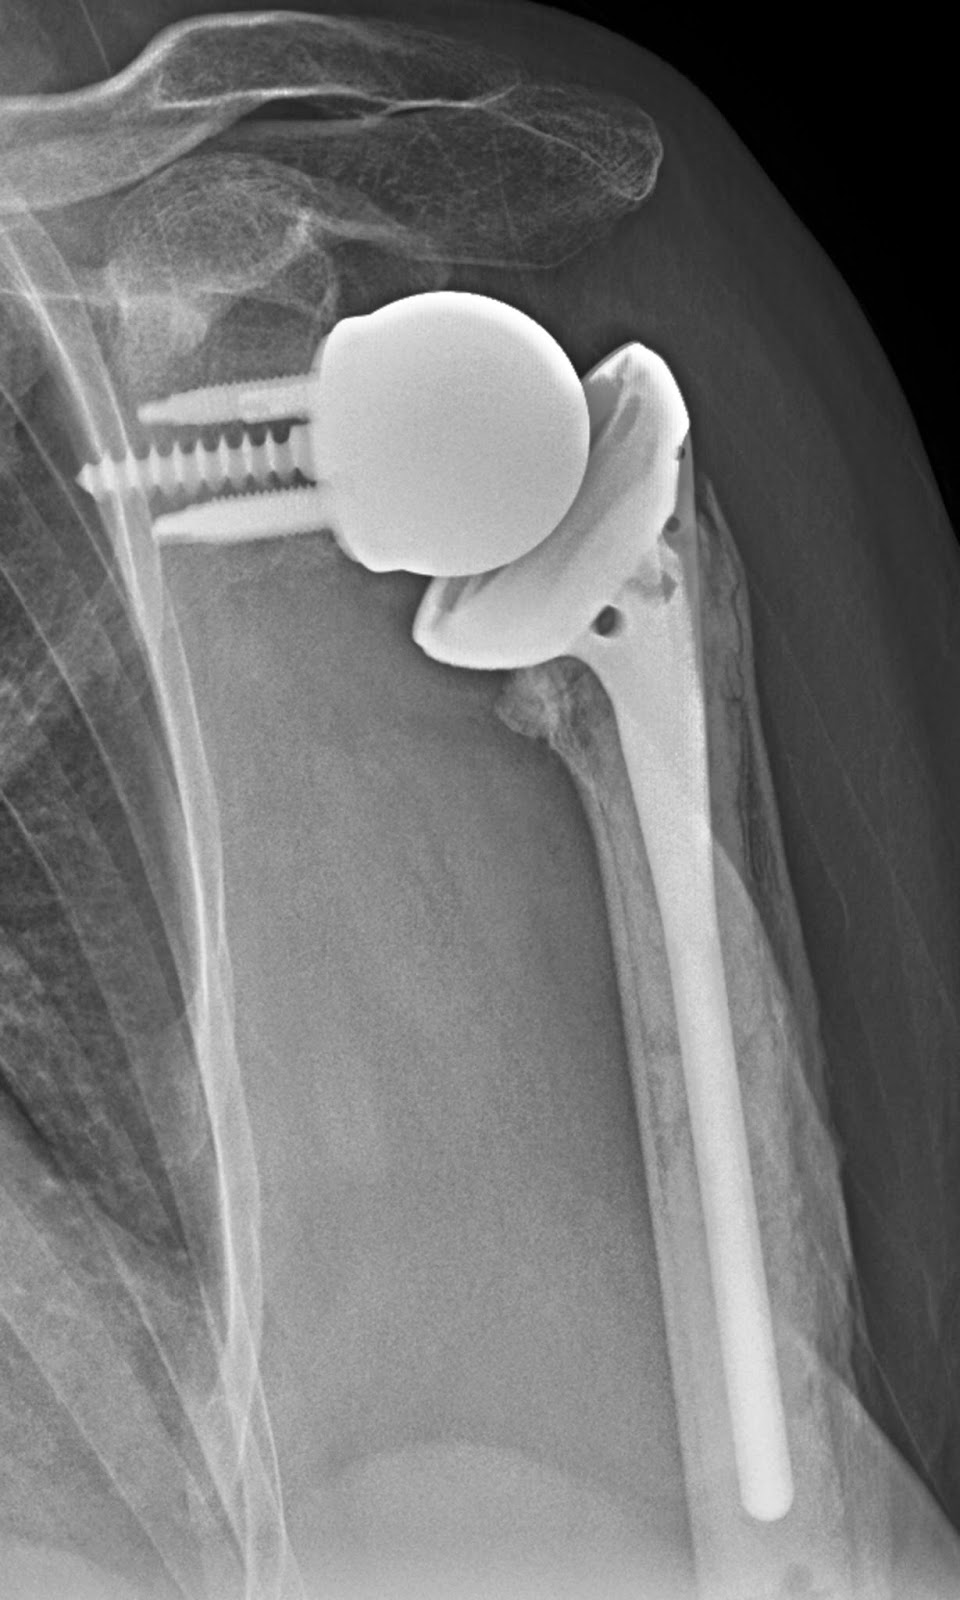

Reverse shoulder prosthesis picture This picture representes reverse shoulder prosthesis.

Fashionable the “reverse prosthesis” the shoulder concerted is still replaced with parts surgery components made exterior of metal and plastic (Figure 3). The big differences between a inverse prosthesis and A standard shoulder refilling is that stylish a reverse prosthetic device, the ball is placed on the socket side of the joint.

[edit on Wikidata] Reverse shoulder replacement is a type of shoulder replacement in which the normal ball and socket relationship of glenohumeral joint is reversed, creating a more stable joint with a fixed fulcrum.